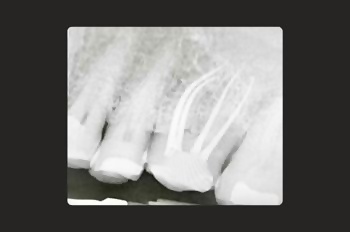

At Moltons Dental, we are committed to delivering the highest precision and care by utilising the Zeiss Extaro microscope for root canal treatments and restorative procedures.

This cutting-edge technology allows us to perform procedures with excellent precision and detail.

The Zeiss Extaro microscope enhances visibility, accuracy, and treatment outcomes, giving our patients the most reliable and predictable experience.